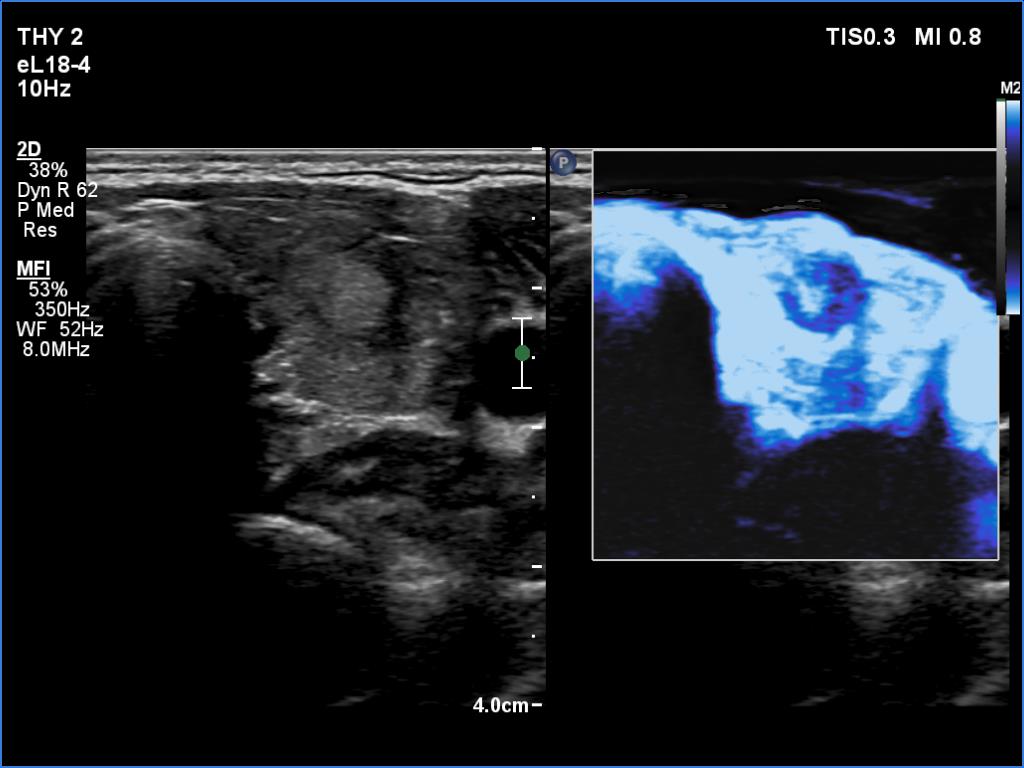

Graves' disease - case 1584

Five years after the first visit (ultrasonographic picture 9)

Left lobe, transverse scan, microflow imaging. The vascularity is hugely increased in the extralesional part while absent in the discrete lesion.